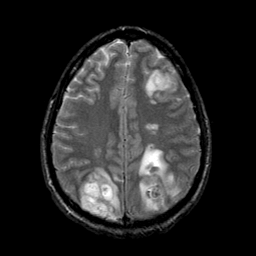

Опишите в каких внутричерепных структурах Вы нашли патологию (Саркома). Необходимо назвать отдел мозга.

вот я отметил посмотри